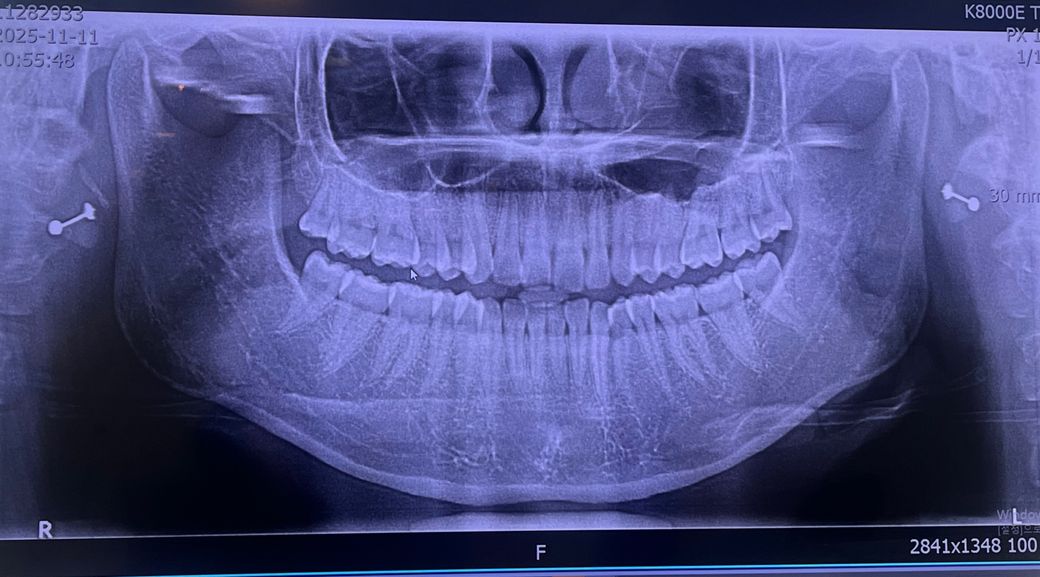

턱관절 엑스레이 한번만 봐주세요 ㅠㅠ

1. 디스크가 빠진건가요? (왼쪽 오른쪽 각각 알려주세요)

2. 뼈가 갈리고 있는 중일까요.. 소리가 나서요

3. 왼쪽과 오른쪽 마모는 어떤가요..?

4. 입을 다물고 힘을 아주조금이라도 주면 드드득 으드득 이런 소리가 나는 원인이 뭘까요? (그리고 이럴 경우 제 턱관절은 어느정도 상태인지 궁금합니다..)

5. 엑스레이 사진보고 양쪽 턱관절이 어떤지 궁금해요..

1. 하악과두 위치는 양호합니다

2. 뼈와 뼈가 직접 만나지는 않습니다. 소리는 하악과두가 디스크(관절)를 지나가면서 내는 소리입니다

3. 마모는 심하지 않습니다

4. 지속적으로 소리가 나고 불편 증상이 있다면 근이완제 약물치료보다 더 적극적인 개입이 필요합니다. 물리치료, 장치치료 등이 필요합니다.